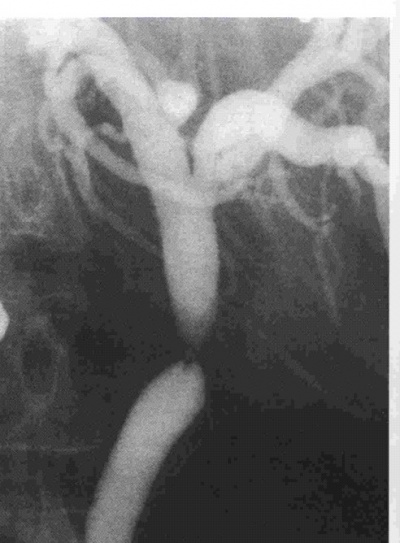

לאחר פתיחת הבטן ובדיקת איברי הבטן ניגשים לכריתת כיס המרה. תחילה מזהים את צינור כיס המרה ואת הכולדוכוס, מזהים את עורק כיס המרה וקושרים אותו בסמוך לכיס המרה. לאחר מכן קושרים את צינור כיס המרה קרוב לכיס המרה, בשלב זה במידת הצורך (ראה הוריות בדרכי מרה) פותחים אותו ומכניסים לתוכו צינורית, שדרכה מצלמים את דרכי המרה (תצלום .21.8). בצילום זה יש לשים לב:

- לאנטומיה של דרכי המרה.

- לליקויים בתוך דרכי המרה, שעלולים להתאים לאבנים או לשאתות בדרכי המרה.

- למעבר חופשי לתריסריון.

- לרוחב הכולדוכוס.

- לרוחב העץ הביליארי התוך-כבדי ולהדגמתו.

בעבר נהגו לבצע צילום דרכי מרה (כולאנגיוגרפיה) תוך-ניתוחית בכל החולים שנכרת בהם כיס מרה. הכולאנגיוגרפיה הקטינה את מספר הפתיחות של דרכי המרה מ- 41% מסיבות קליניות ל- 25% מהחולים, וכמו-כן נתגלו כ- 4% מהלוקים באבנים בדרכי המרה בלא כל תסמינים אחרים. במשך השנים, עם התפתחות ה- EUS וה- ERCP, המאפשר זיהוי אבנים, הן לפני הניתוח והן לאחריו וטיפול בהן, ההוריות לצילום תוך-ניתוחי של דרכי המרה הצטמצמו ביותר וכוללים חולים בהם ה- ERCP לא הצליח טכנית, או שנתגלה פגם בדרכי המרה שלא טופל לפני הניתוח, חולים תסמיניים כגון חולי צהבת, חולים הלוקים בכולדוכוס מורחב של יותר מ- 16 מ"מ, במקרים שבהם האנטומיה בניתוח אינה ברורה. כולאנגיוגרפיה באותן הוריות ניתן לבצע גם בחולים המנותחים בשיטה לפרוסקופית.